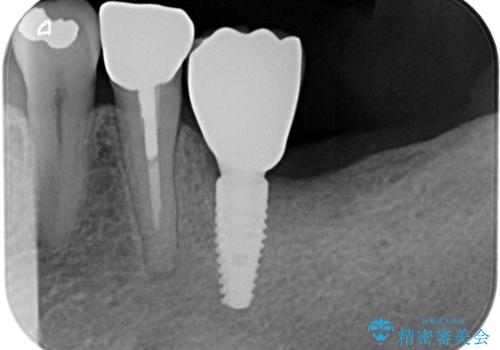

残根状態の歯を抜歯後、抜歯窩の治癒を待ちインプラントを埋入しています。

アバットメントの材質は咬合力を考慮しチタン合金にしました。

被せ物はオールセラミッククラウンを入れています。

患者さんから、インプラント埋入オペ後も痛みが殆どなく、咬めるようになったので治療をして良かったですと言って頂けました。